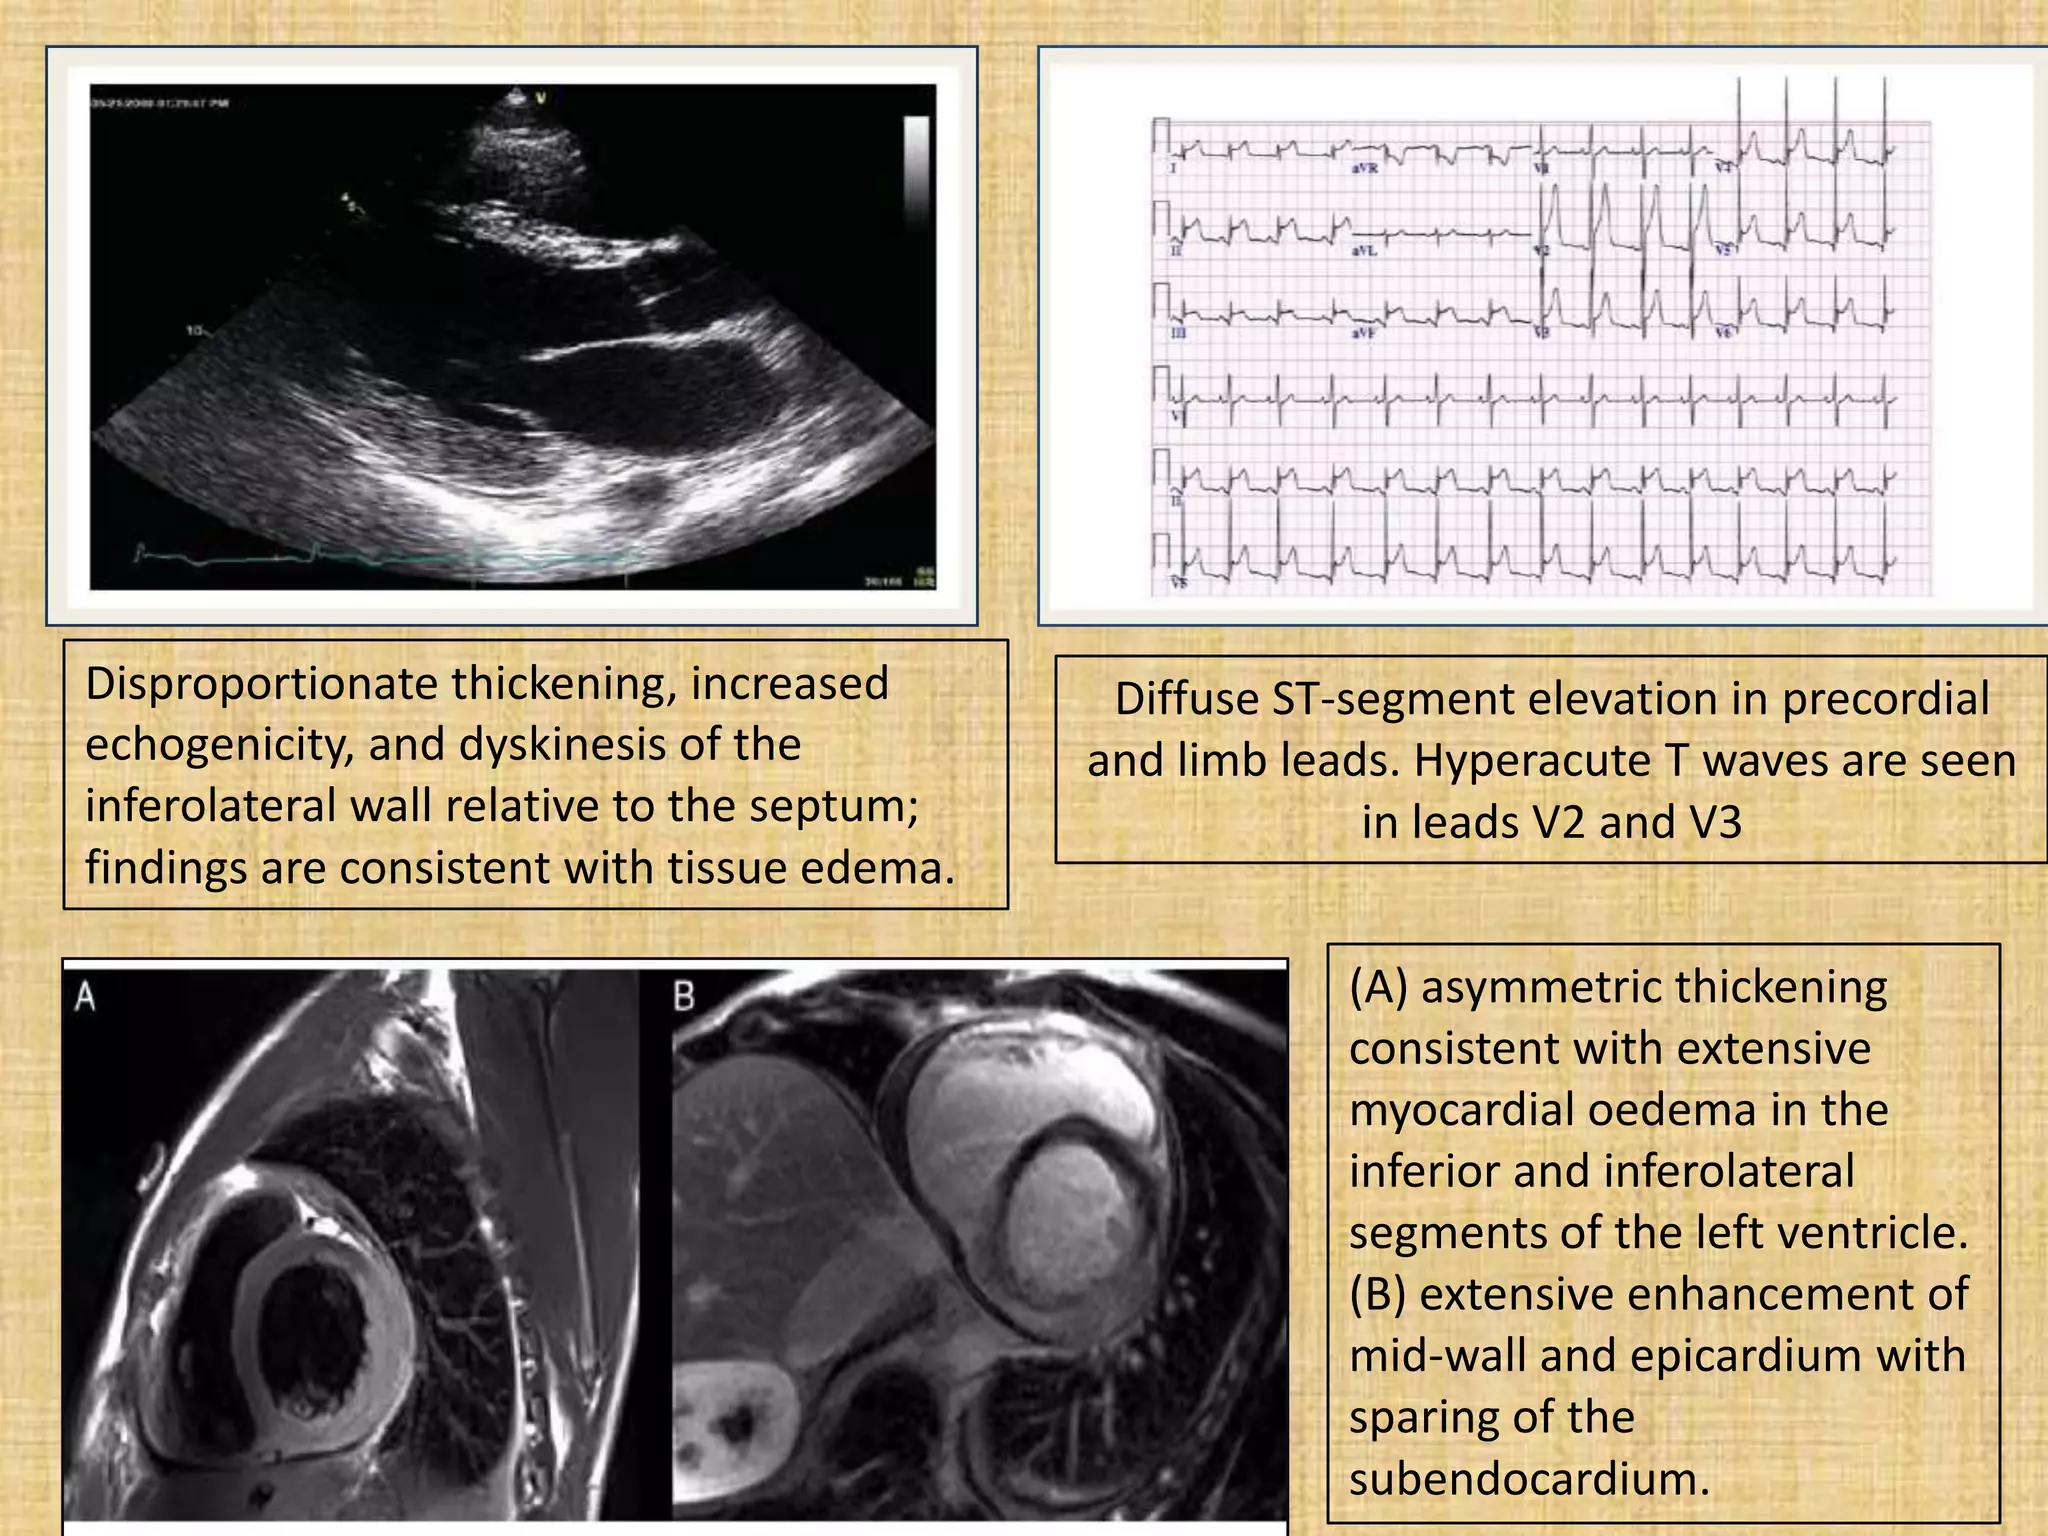

When is a heart attack

Viral myocarditis may have various

clinical presentations, sometimes

mimicking acute myocardial

infarction or ischaemia.

Disproportionate thickening, increased

echogenicity, and dyskinesis of the

inferolateral wall relative to the septum;

findings are consistent with tissue edema.

Diffuse ST-segment elevation in precordial

and limb leads. Hyperacute T waves are seen

in leads V2 and V3

(A) asymmetric thickening

consistent with extensive

myocardial oedema in the

inferior and inferolateral

segments of the left ventricle.

(B) extensive enhancement of

mid-wall and epicardium with

sparing of the

subendocardium.